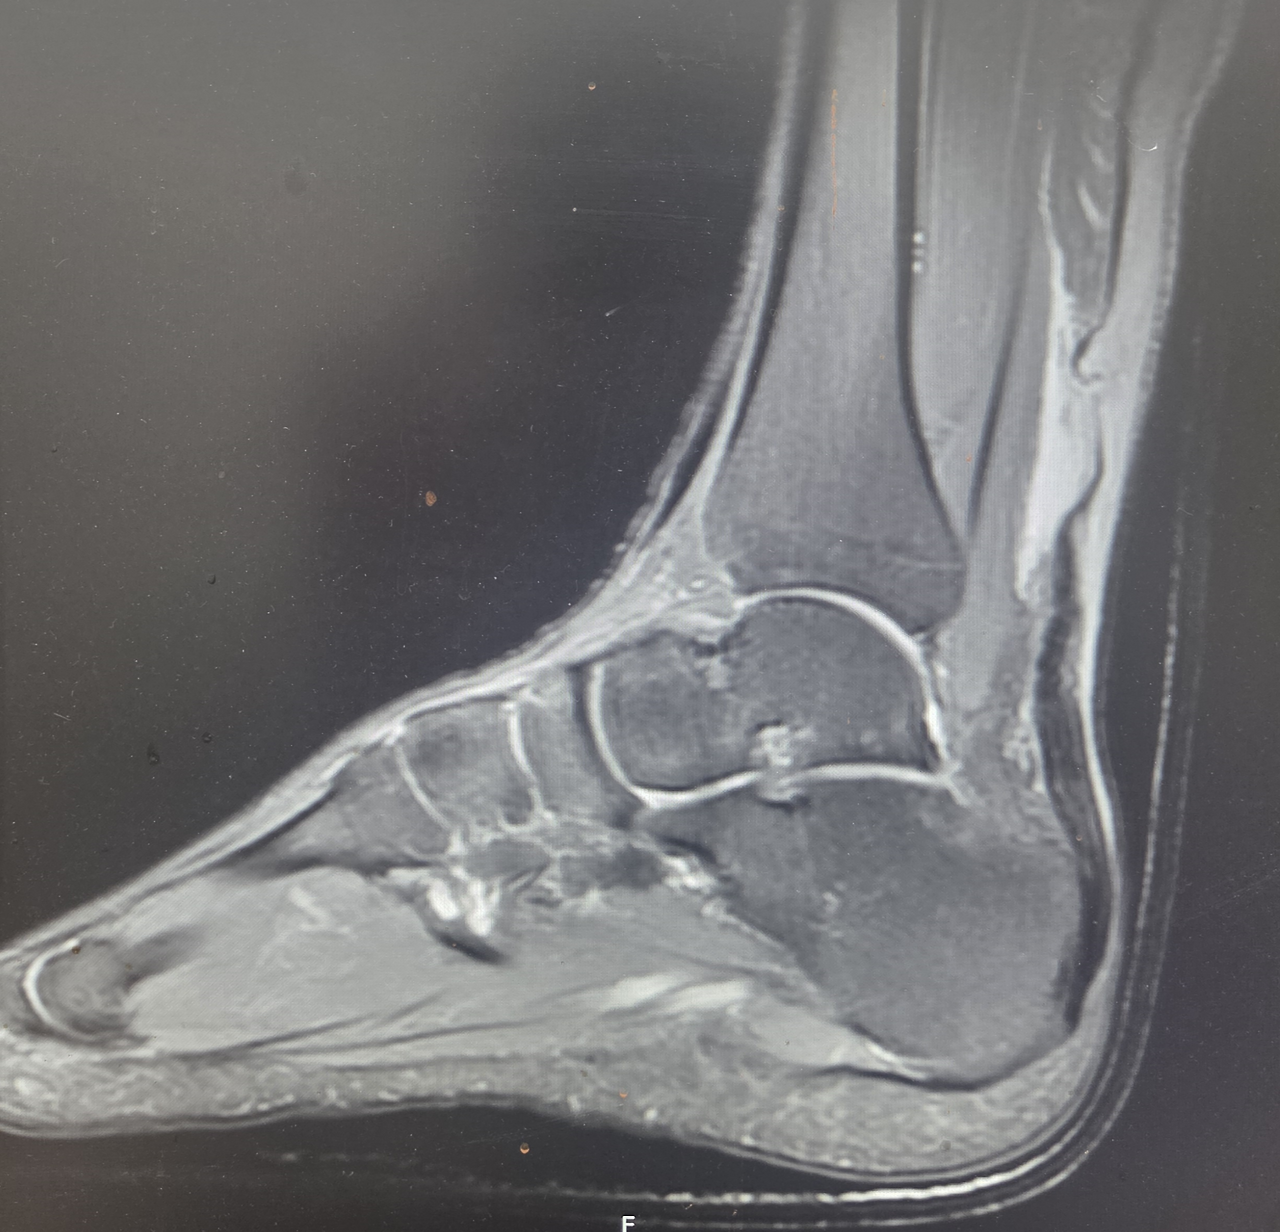

현재 상태와 치료 방향에 대해 환자와 보호자와 충분히 상의한 뒤 재수술을 진행하기로 결정하였다. 환자의 나이를 고려했을 때 절개 부위는 더 커질 수 있지만, 이후 적극적인 재활을 통해 기능을 최대한 회복하는 것이 더 중요하다고 판단하였다.

수술 당시 힘줄은 1차 봉합이 어려울 정도로 심하게 파열된 상태였다.

하지만 힘줄이 직접 이어져 회복되는 것이 이후 강도와 기능 면에서 훨씬 유리하기 때문에 먼저 갈라진 힘줄들을 하나로 모아 보강하는 과정을 거쳤다. 이후 타가건을 이용하여 봉합 부위를 추가로 보강하는 방식으로 수술을 진행하였다.

수술 후 발목을 움직여도 다시 파열이 일어나지 않을 정도의 강도를 확인한 뒤 수술을 마쳤다.